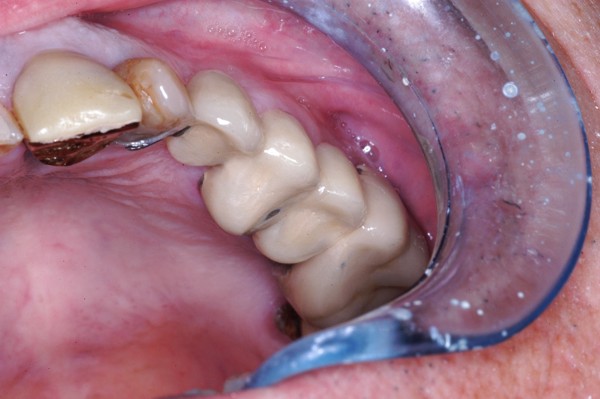

MUCHO SE HA HABLADO HASTA HOY DE LOS DISTINTOS ESQUEMAS OCLUSALES A USAR. SIN EMBARGO , HAY ALGO DE QUE ADOLECEN LAS LOS TRABAJOS PROTÉTICOS OBSERVADOS EN MÚLTIPLES LABORATORIOS DE NUESTRO MEDIO , COMO ASI DE MUCHAS PUBLICACIONES DE LOS ÚLTIMOS TIEMPOS , OLVIDANDO UN CONCEPTO TAN BÁSICO COMO EVIDENTE: PARA QUE SIRVEN LOS DIENTES. OBSERVAMOS A MENUDO GRANDES ELEVACIONES DE SENO A FIN DE LOGRAR IMPLANTAR LO IMPOSIBLE….LATERALIZACIONES DE NERVIO DENTARIO INFERIOR CON FINES SIMILARES…EXTENSAS PRÓTESIS CANTILEVER PARA REPONER LA CASI TOTALIDAD DE UNA ARCADA…Y UN SINFÍN DE RECURSOS QUE SE ACERCAN AL CRITERIO DE «ALGO HAY QUE PONER…» Y SE ALEJAN DEL SERIO SENTIDO DE «REHABILITAR». SABEMOS QUE SON MÚLTIPLES LAS FUNCIONES QUE EL SISTEMA DENTARIO CUMPLE, PERO LA FUNDAMENTAL ES MASTICAR. EN ESE SENTIDO DESDE LOS RUMIANTES, HASTA LOS CARNÍVOROS TIENEN SUS PROPIOS PATRONES A SEGUIR. EN EL CASO DEL HOMBRE, CON UNA ARTICULACIÓN TEMPOROMANDIBULAR TAN COMPLEJA Y PAUSIBLE DE DISFUNCIONES, COMO DE UN COMPLEJO MUSCULAR NECESITADO DE UNA LONGITUD ADECUADA PARA SU ORTOFUNCIÓN, LA CAPACIDAD DE MASTICAR SE VE A MENUDO ALTERADA POR LOS INNUMERABLES TRABAJOS PROTÉTICOS QUE A DIARIO SE REALIZAN EN EL MUNDO, QUE CARECEN DE LOS PATRONES NECESARIOS PARA QUE ESA FUNCIÓN SE DESARROLLE CORRECTAMENTE. LAS SUBFUNCIONES DE : INCIDIR-DESGARRAR-DISCERNIR EL ALIMENTO Y MOLER, ,PARA FINALMENTE DEGLUTIR, QUE CUMPLEN LAS DISTINTAS PIEZAS DENTARIAS , CONSTITUYEN UN CAPÍTULO DE LA ODONTOLOGÍA TAN BÁSICO Y EVIDENTE, COMO OLVIDADO . ES A MI CRITERIO FUNDAMENTAL ; PENSAR LAS DISTINTAS REHABILITACIONES ORALES POSIBLES, EN TÉRMINOS DE : EFICACIA MASTICATORIA CUANDO A MENUDO OBSERVAMOS CARAS PALATINAS DE LOS ANTERIORES CLARAMENTE CONVEXAS, O CUANDO LAS SUPERFICIES OCLUSALES DE LOS POSTERIORES SE CONSTRUYEN CON CÚSPIDES GRADO CERO, CON FINES DE MINIMIZAR LAS FUERZAS EXPULSIVAS DE UNA PRÓTESIS O LAS FUERZAS TANGENCIALES A LOS IMPLANTES, …LA EFICACIA MASTICATORIA, DISMINUYE SENSIBLEMENTE , CUANDO NO SE PROVOCAN DISFUNCIONES IATROGÉNICAS A VECES MAS DIFÍCILES DE RESOLVER QUE EL ESTADO INICIAL DE LA BOCA. DE LA MISMA MANERA, LA CONSERVACIÓN PROLONGADA DE PIEZAS EN ESTADO TERMINAL, MUCHAS VECES PROVOCA LA PÉRDIDA EXAGERADA DE HUESO ALVEOLAR, MANTENIENDO LOS MISMOS CON SUPRAESTRUCTURAS QUE AGRAVAN LA SITUACIÓN. SI BIEN ES CIERTO, QUE LA CONSERVACIÓN DE PIEZAS DENTARIAS , MUCHAS VECES EN «ESTADO CAÓTICO», NOS SIRVEN PARA SOPORTAR ELEMENTOS PROVISIONALES DE ALTA EFICACIA DURANTE EL TRATAMIENTO REHABILITADOR….Y QUE LAS MISMAS ADQUIEREN ESTADOS MUCHO MAS BENÉFICOS DURANTE SU PROVISORIA FUNCIÓN, TAMBIÉN ES CIERTO, QUE CON VISTAS A UNA MAYOR «EFICACIA MASTICATORIA», LA CONSERVACIÓN DEL HUESO RESIDUAL POST EXTRACCIÓN, ADECUADAMENTE TRATADO , SUELE SER DE MAS UTILIDAD , QUE LA CONSERVACIÓN PROLONGADA DE ELEMENTOS DENTARIOS ALTAMENTE DESTRUIDOS. SALZMAN, EN 1.947 COMPROBÓ QUE PUEDE NO EXISTIR EL MOVIMIENTO HORIZONTAL MANDIBULAR DURANTE LA MASTICACIÓN DE ALIMENTOS BLANDOS, MIENTRAS QUE LOS ALIMENTOS DUROS QUE NECESITAN MAS PRESIÓN, DAN FORZOZAMENTE LUGAR A LA TRANSTRUSIÓN. JANKELSON, HOFFMAN Y HENDRON, EN 1.953, ESTABLECIERON QUE LA MASTICACIÓN, BILATERAL ALTERNADA, ERA NECESARIA PARA LA MANUTENCIÓN DE LAS ESTRUCTURAS DE SOPORTE, Y QUE LAS MASTICACIONES UNILATERALES O PROTRUSIVAS ERAN PRODUCTO DE INTERFERENCIAS OCLUSALES. CIERTOS ESTUDIOS REALIZADOS CON CINEFLUOROSCOPÍA HAN DEMOSTRADO QUE NO EXISTE NINGÚN CONTACTO DENTARIO DURANTE LA MASTICACIÓN . NO OBSTANTE ADAMS Y ZANDER EN 1.964, CON MÉTODOS DE BASADOS EN LA MULTIPLICIDAD DE ESTUDIOS PRODUCIDOS ACERCA DE LA FISIOLOGÍA DE LA MASTICACIÓN , ES IMPENSABLE HOY, A LA ALTURA DE LOS CONOCIMIENTOS ACTUALES , ESCAPAR A LA NORMA INELUDIBLE DE FORMA = FUNCIÓN POR ELLO ES NECESARIO , ANALIZAR LAS REHABILITACIONES EN FORMA GLOBAL E INTESIVAMENTE , YA QUE , POR EJEMPLO , LA SIMPLE INSTALACIÓN DE IMPLANTES DENTALES , POR MUY INTEGRADOS QUE ESTEN , DE NADA SIRVEN SI NO EXISTE UNA CONGRUENCIA ENTRE LAS FORMAS QUE CUMPLAN LAS FUNCIONES ESPECÍFICAS PARA LAS CUALES HA SIDO CREADO EL SISTEMA. EN LAS SIGUIENTES FOTOGRAFÍAS PERTENECIENTES A UN MISMO CASO , SE OBSERVA CLARAMENTE QUE SI BIEN SE HAN COLOCADO LAS PIEZAS FALTANTES EN UN ÁREA EDÉNTULA , DE POCO SERVIRÁN YA QUE LA GUIA CANINA DEL LADO OPUESTO ES INEXISTENTE, ADEMÁS DE QUE LAS SUPERFICIES OCLUSALES DIFÍCILMENTE CUMPLAN CON LA EFICACIA MASTICATORIA. EN LA MASTICACIÓN OMNÍVORA LOS CONTACTOS OCLUSALES SON INEXISTENTES SALVO EN LA ÚLTIMA FASE DEL CICLO MASTICATORIO. EL CICLO MASTICATORIO CONSTA DE DISTINTAS FASES DE LAS CUALES LA INICIAL , CONSISTE EN LA: POSTERIORMENTE , LA MANDIBULA EJERCE UN MOVIMIENTO LATERAL HACIA EL LADO (LADO DE TRABAJO) DONDE SE HA UBICADO EL ALIMENTO : A CONTINUACIÓN LA MANDIBULA LATERALIZADA COMIENZA EL CIERRE , HASTA CONTACTAR LOS CANINOS ENTRE SI : DONDE EL SUPERIOR SEÑALA EL CAMINO A SEGUIR DEL CANINO INFERIOR (QUE ES SOLIDARIO A LA MANDIBULA TODA), DESDE EL PUNTO DEL PRIMER CONTACTO (BORDE A BORDE CANINO , O SUS CERCANÍAS ), HASTA AQUEL PUNTO TERMINAL ,DEL RECORRIDO CANINO QUE SEÑALA LA: …….. DEL RESTO DE LAS PIEZAS. DURANTE ESA APROXIMACIÓN HACIA LA MÁXIMA INTERCUSPIDACIÓN ( LO QUE ES LO MISMO QUE HACIA LA RELACIÓN CÉNTRICA EN UNA OCLUSIÓN ORGÁNICA..) , LOS REBORDES MARGINALES MESIALES Y DISTALES , JUNTO A LAS TRIANGULARES INTERNAS DE LAS PIEZAS POSTERIORES DESBRIDAN EL ALIMENTO EN CICLOS CADA VEZ MAS PEQUEÑOS, A MEDIDA QUE EL ALIMENTO SE DESTRUYE. LAS PIEZAS DENTARIAS SE VAN APROXIMANDO ENTRE SI CADA VEZ MAS , INTERDIGITANDO SUS CÚSPIDES , SEGÚN EL MECANISMO ANTERIOR , HASTA ALCANZAR UN BOLO ADECUADO PARA DEGLUTIR. DE LA MISMA MANERA QUE LO HACE UNA TIJERA. ASI, ES COMO ACTUAN LAS CÚSPIDES DENTARIAS ¿CUAL SERÁ ENTONCES EL EFECTO DE UNA MASTICACIÓN CARENTE ABSOLUTAMENTE DE ANATOMÍA? FRENTE A UNA MASTICACIÓN QUE OPERE SEGÚN: FORMA = FUNCIÓN ¿? ES EVIDENTE QUE LA INEFICACIA PRODUCTO DE LA FALTA DE ANATOMÍA ADECUADA REDUNDARÁ EN UN MAYOR ESFUERZO MASTICATORIO , Y SERÁ EL RESTO DEL APARATO DIGESTIVO QUIEN SE ENCARGUE DE LAS DESTRUCCIÓN DE LOS ALIMENTOS PARA QUE ESTOS SEAN DIGERIDOS. REHABILITAR LAS SUPERFICIES OCLUSALES , COMO ASI REPONERLAS CON UN CRITERIO ANATÓMICO FUNCIONAL , DONDE LA ALTURA CUSPÍDEA , LA GUÍA CANINA, LA CREACIÓN DE ESPACIOS UNIFORMES DURANTE EL FENÓMENO DE LUCE , LA DISCLUSIÓN ABSOLUTA DE TODAS LAS UNIDADES DE OCLUSIÓN DURANTE UNA TRANSTRUSIÓN , TANTO DEL LADO ACTIVO COMO DEL NO ACTIVO, EN ARMÓNICA CONGRUENCIA CON LA LONGITUD MUSCULAR Y EL FISIOLOGISMO ARTICULAR , CONSTITUYEN LAS BASES PARA CONSTRUIR REHABILITACIONES QUE REPONGAN Y MANTENGAN LA EFICACIA MASTICATORIA.

FIG 12